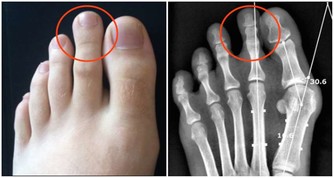

健康教育中心專家沈雁英教授說:絕大多數65歲以上的老年人,關節已經退化,上下樓梯或爬山時,膝關節承受的人體重量是平時的3~5倍,這會加重關節老化。她建議,老年人最好不要選擇爬樓梯這個鍛煉方法,如果需要上下樓,一定要抓穩扶手。